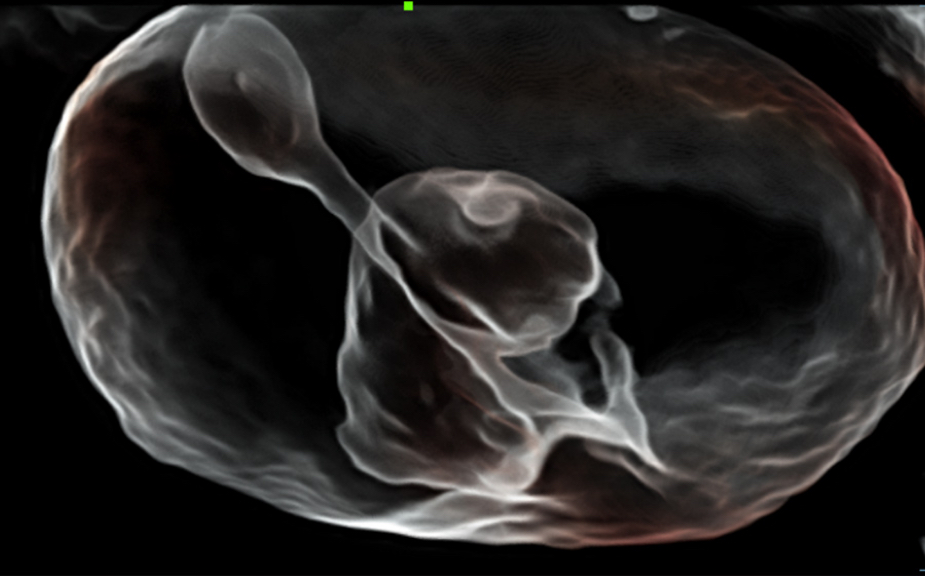

ZST + Taraf?ndan Desteklenen Eksiksiz ??z├╝m

ZST+ platformu, ultrason evrimini temsil eden ola?an├╝st├╝ bir yeniliktir. Ultrason ?l?├╝mlerini geleneksel ???n bi?imlendirmeden kanal verilerine dayal? i?lemeye d?n├╝?t├╝r├╝r. Mekansal ??z├╝n├╝rl├╝k, zamansal ??z├╝n├╝rl├╝k ve doku homojenli?i aras?ndaki geleneksel dengeli s?n?rlaman?n ├╝stesinden gelir ve kesintisiz iyile?tirmelerle s?n?rs?z g?r├╝nt├╝leme ??z├╝mleri i?in ola?an├╝st├╝ g?r├╝nt├╝ kalitesi sunar.